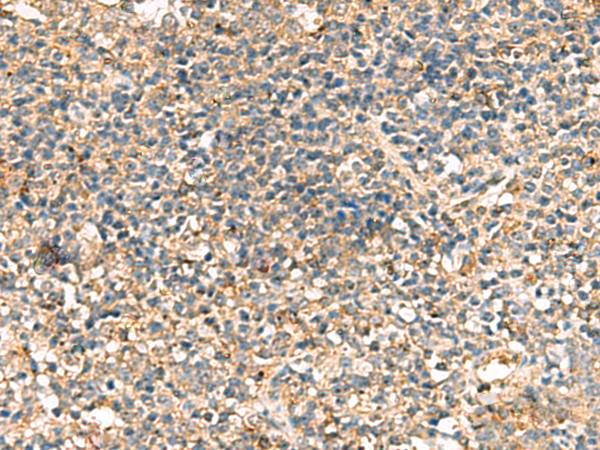

分类: 科研抗体货号: P11099别名: PRP; TSA; PRX2; PTX1; TPX1; NKEFB; PRXII; TDPX1; NKEF-B应用: WB,IHC反应种属: Human, Mouse, Rat